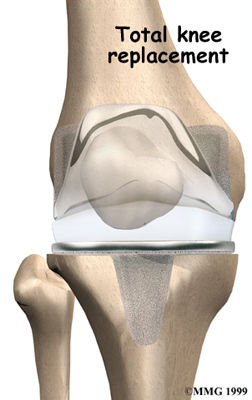

Artificial Knee Replacement

An artificial knee replacement is the ultimate solution for advanced knee OA.

Surgeons prefer not to put a new knee joint in patients younger than 60. This is because younger patients are generally more active and might put too much stress on the joint, causing it to loosen or even crack. A revision surgery to replace a damaged prosthesis is harder to do, has more possible complications, and is usually less successful than a first-time joint replacement surgery.

Related Document: FYZICAL Naples (Pelican Bay)'s Guide to Artificial Joint Replacement of the Knee